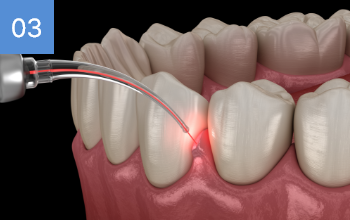

상악의 경우 단순매복으로 발치 및 동시에 하악 잇몸뼈에

깊게 박혀잇는 고난이도 케이스, 잇몸절개 후 치아 분리하여

발치하였으며